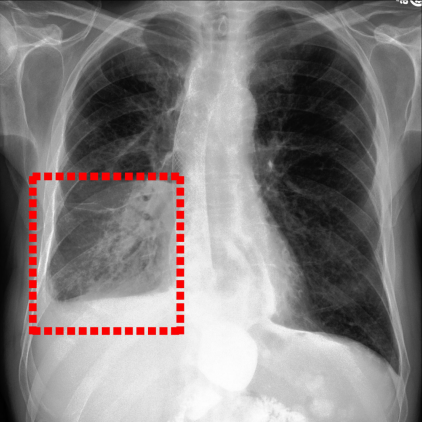

Refer to caption

Figure 4: Visualization of attention maps generated by PLAN on MS-CXR dataset. The red boxes indicate the ground truth for disease localization, while the heatmaps highlight regions with higher activation weights with disease-related phrases in the text.

IV-B1 Phrase Grounding

Phrase grounding associates textual phrases (e.g., disease descriptions or anatomical terms) with corresponding regions in medical images, offering precise diagnostic insights and enhancing model interpretability. Table II presents the phrase grounding results on the MS-CXR dataset. Using the Contrast-to-Noise Ratio (CNR) [27] as the evaluation metric, PLAN achieved the highest CNR across eight disease categories, outperforming MGCA and PRIOR. Heatmaps generated with Grad-CAM (Figure 4) further illustrate PLAN’s ability to accurately localize lesion sites and align disease-related phrases with image regions. Additional comparisons with baseline methods can be found in Figure 5. These findings highlight PLAN’s superior precision and interpretability in phrase grounding tasks.